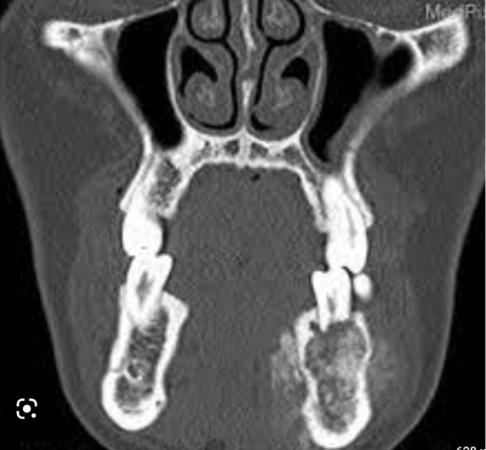

Q

CBCT X-ray given, patients presents with swelling & pain, what is the likely diagnosis?

A

osteosarcoma